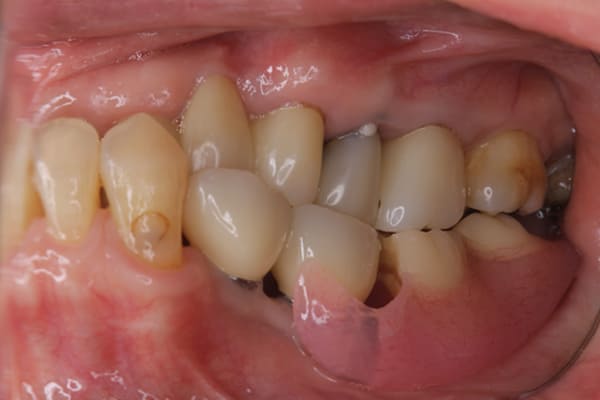

上下互い違いで咬む歯同士がない状態のため、柔らかいものを舌で潰され召し上がっておられました。

かみ合わせがなく、すれ違い咬合と言われる難症例に分類される状態でした。

上の歯は重度歯周炎でぐらぐらで、お痛みも繰り返しており、抜歯が必要な状態でした。

検査の結果、下の3本のうち、2本は何とか根は残せる状態であったため、虫歯の治療、根の治療を行い残すことに努めました。

上下の歯同士のかみ合わせがない状態で長年過ごされていましたので、当初はどこで咬んだら良いかわからない状態でしたが、治療用入れ歯を用い、調整を行い、本来のかみ合わせに戻すことが可能になりました。

初めての入れ歯が総入れ歯の場合は、大きな違和感を感じられる方が多いですが、上顎に金属を用いた入れ歯にすることで、厚みを薄くし違和感を抑え、お食事での温熱も感じられるようになりました。

下の総入れ歯は外れやすいため大きな虫歯はありましたが、虫歯治療を行い、根のみ残せた2本の歯に磁石を利用することで歌われた際も外れない入れ歯の設計としました。

下顎は舌があるため、上顎と比較すると総入れ歯の場合、外れやすい傾向があります。患者様はまだお若く、お肉がお好きだったとのこと、またお歌もご趣味とのことで、ご相談の上、なるべく外れない設計としました。

磁石を用いた入れ歯の設計により上下の入れ歯は、お食事やお歌を歌われ大きなお口を開けても外れない状態が可能になりました。

当初、ハンバーガーを召し上がりたいと仰っていましたが、今ではステーキも召し上がられ、カラオケでも入れ歯は外れず、滑舌が全く変わったと喜んで下さりました。